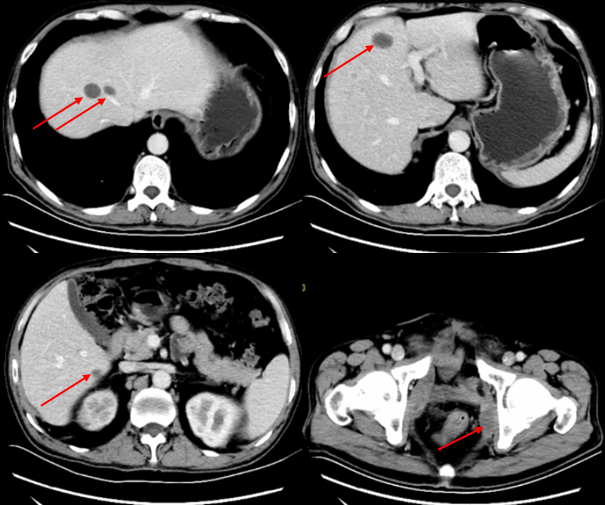

2019年3月1日复查全腹部CT增强扫描示:肝及盆腔内多发转移瘤。对比2019.1.25前片,肝内部分病灶及盆腔病灶缩小(图4)。

图4 患者肝脏及盆腔转移瘤较前明显缩小(2019年3月1日)

2019-3-29复查全腹部CT增强示:肝脏及盆腔内多发转移瘤;对比2019.3.1前片,肝脏及盆腔转移瘤均明显缩小(图5)。后规律复查CT,表现基本相仿。

图5 患者肝脏及盆腔转移瘤继续缩小,疗效评估为部分缓解(PR;2019年3月29日)

患者2019年1月25日(发现盆腔多发转移病灶后1个月)检查发现肝脏出现多发转移性肿瘤,考虑患者病情进展迅速且疾病负荷较大,而免疫治疗起效相对较晚,调整治疗方案为信迪利单抗免疫治疗联合白蛋白紫杉醇化疗。治疗期间定期复查,肝脏转移灶和盆腔病灶明显缩小及消失,疗效PR。截至2019年9月,患者共接受白蛋白紫杉醇(100mg)qw化疗23次,末次化疗时间2019年8月,信迪利单抗(200mg)q3w治疗13次,末次治疗时间2019年9月18日,一线治疗PFS为9个月。